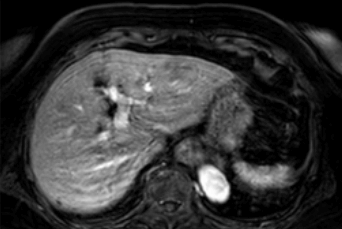

현재의 기술 발전으로 한 번 호흡 정지를 할 수 있는 시간(15-20초) 내에 MRI로 영상화할 수 있지만, 그 사이에 움직임이 발생하면 아래 그림과 같이 영상이 뿌옇게 되거나 물결치듯 보이게 되어 작은 간암의 경우 진단이 어려울 수 있습니다.

간 MRI 촬영 중 호흡 조절정도의 차이에 따른 영상의 질차이 왼쪽의 MRI는 촬영 중심한 호흡 운동으로 인해물결 모양의 허상이 심한 반면 오른쪽의 MRI는 촬영 중 호흡이정지가양호해영상이보다 깨끗하게 보입니다.